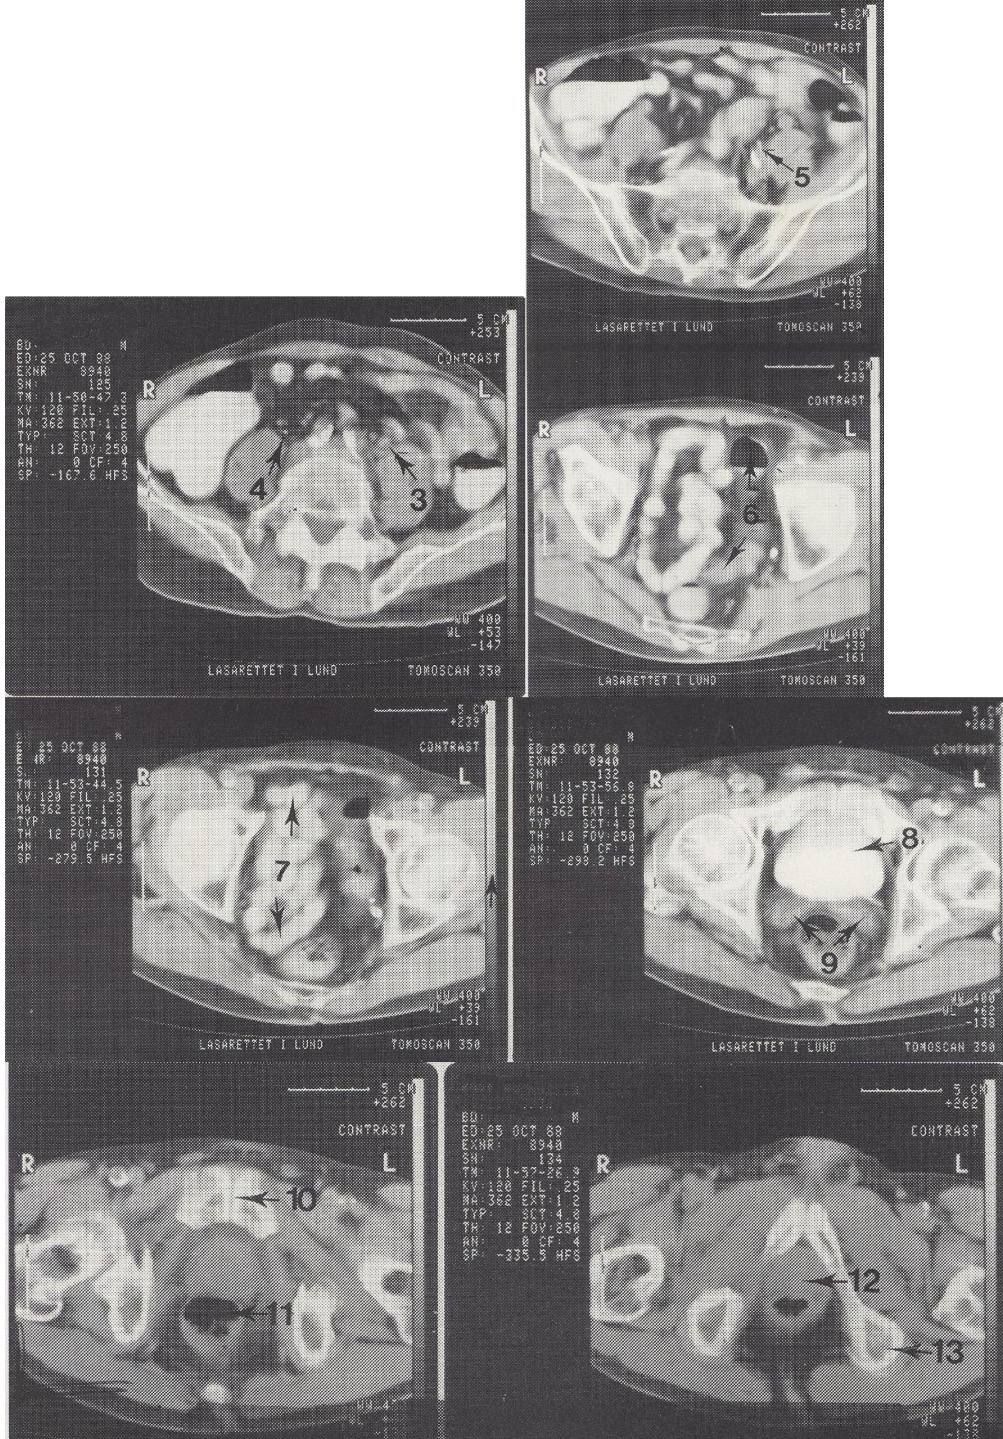

8

Vesica urinaria (šlapimo pūslė, užpildyta kontrastu)

9

Vesiculae seminales (sėklinės pūslelės)

Metodika

KT pjūviai nuo juosmens slankstelių iki gaktinės sąvaržos apačios. Suleistas intraveninis kontrastas (išryškina šlapimo takus) ir išgertas kontrastas (išryškina žarnyną).

Radiniai

Gausūs apkalkėjimai (kalcifikatai) aplink pilvinę aortą ir vidines klubo arterijas. Kairysis šlapimtakis matomas priešais m. psoas major, jis šiek tiek išsiplėtęs.